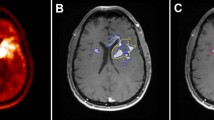

In patients in whom the diagnosis confirmed tumour progression (nine patients), all corresponding FET PET scans showed increased uptake (TBRmax 3.5 ± 0.6, range 2.5–4.4; TBRmean 2.7 ± 0.7, range 2.0–4.0). In four of these nine patients, tumour progression was diagnosed histologically. Imaging and histology in a representative patient (patient 11) are presented in Fig. 1. In patients in whom the diagnosis of tumour progression was confirmed clinically (five of nine patients), the median follow-up was 4 months (range 3–6 months). Static data on FET uptake in the lesions are presented in Table 1. Furthermore, in three of these nine patients, a baseline FET PET scan prior to initiation of neurooncological treatment including TTFields was available (patients 3, 4 and 6; Table 1). Compared with baseline, either a significant increase in the metabolically active tumour volume (patient 4; Fig. 2) or a significant increase in TBR (patients 3 and 6) on FET PET were observed. In patient 3, TBRmax increased from 3.2 to 3.9 (22%) and TBRmean from 1.9 to 2.3 (21%). In patient 4, TBRmax increased from 1.9 to 2.8 (47%), and TBRmean from 1.7 to 1.9 (12%). In patient 4, the metabolically active tumour volume increased significantly from 9 ml (at baseline) to 42 ml (at 9 months; Fig. 2).

Contrast-enhanced MRI, FLAIR-weighted MRI and PET-MRI fusion images (top row) in a 55-year-old man with glioblastoma at the time of progression treated with lomustine and TTFields (patient 11). In line with the MRI findings, FET PET shows increased metabolic activity (TBRmax 4.4, TBRmean 4.0). Histology (haematoxylin and eosin stain, bottom) after resection is consistent with progressive glioblastoma